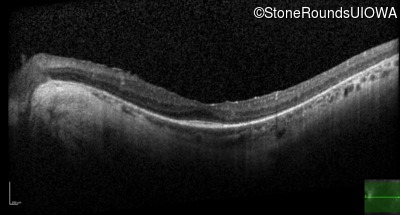

Optical Coherence Tomography - Left - 20/50 +2

Exemplar / OCT Stack

OCT Stack